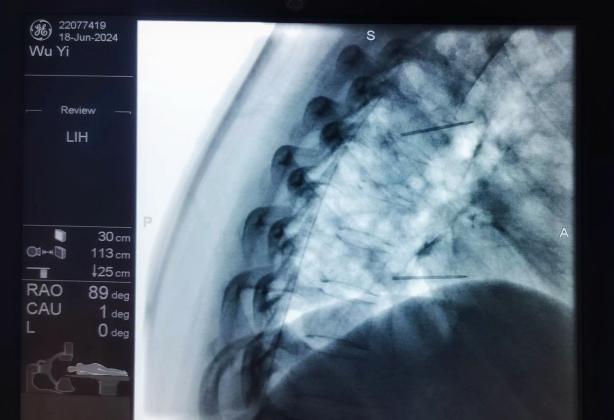

ac874aa18aee42e58f8890dd86cc1a27.Jpeg  09566eb81ad84804af008e90e5297638.Jpeg

椎間盤射頻消融術(shù)、膠原酶椎間盤化學(xué)消融術(shù)